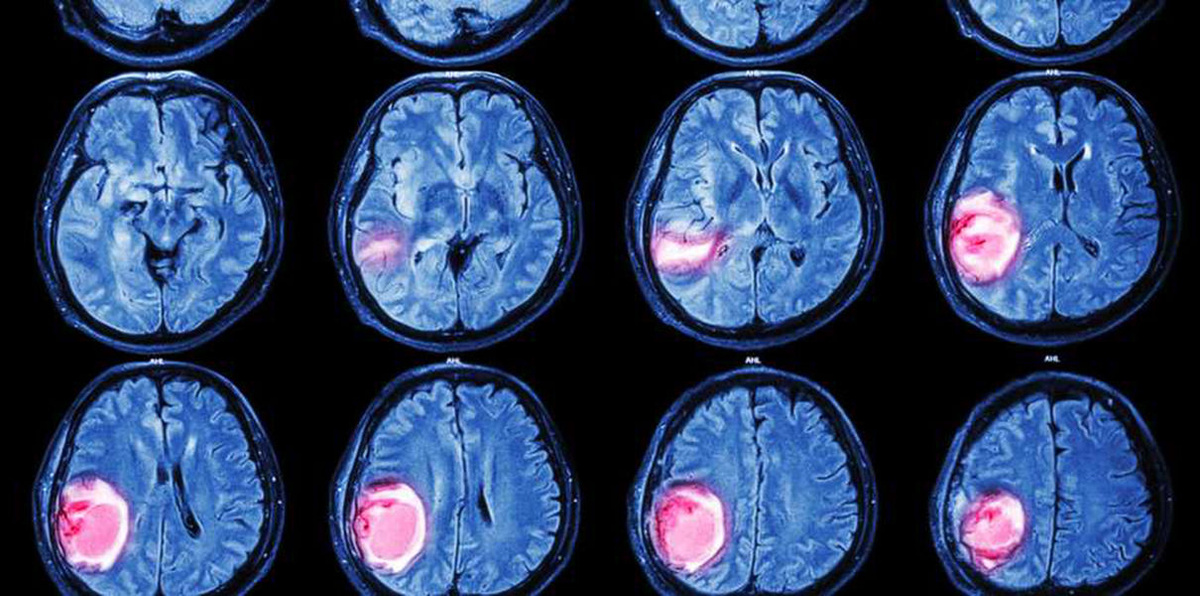

На учёте у первоуральских онкологов состоят более 50 человек со всего Западного округа со злокачественными новообразованиями головного мозга, из них 38 – под наблюдением врачей более 5 лет. Проходят химиотерапию в горбольнице на сегодня 4 пациента.

Рак мозга – злокачественная опухоль в области головного мозга. Различают около 130 видов опухолей данного органа. Одной из причин заболевания может быть стресс и недосыпание.

Развитие рака головного мозга может быть обусловлено разнообразными причинами: наследственность, радиоактивное облучение, токсическое воздействие ртути или свинца, травмы головы, вредные привычки, повышенное артериальное давление, частые или сильные стрессы, недосыпание и постоянное переутомление.

Чаще всего опухоли головного мозга диагностируют у людей старше 45-50 лет.